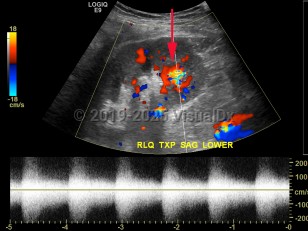

An arteriovenous fistula is an abnormal connection between arteries and veins that may be congenital, surgically induced for hemodialysis or as a rare complication from cardiac catheterization, or acquired from traumatic penetrating injury, infection, or malignancy. Congenital arteriovenous fistulas in the brain may be associated with abnormalities of the vein of Galen. Acquired forms typically occur in lower extremities, and, with long-standing fistulas, symptoms of edema and limb ischemia can occur. Many fistulas repair spontaneously and only require observation, but surgical repair or ultrasound-guided compression is indicated for symptomatic patients.

Arteriovenous fistula